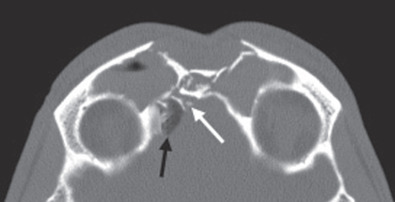

The gold standard radiographic examination for traumatic injuries of the facial skeleton is a thin cut (≤1 mm) computed tomography (CT) scan. To help improve diagnostic accuracy, these images should be reformatted into coronal, sagittal, and 3-dimensional reconstructions. The axial images are preferred for evaluation of the anterior and posterior table ( Fig. 1.7.4 ); sagittal images for the frontal sinus outflow tract and skull base ( Fig. 1.7.5 ); and the coronal images for the orbital roof/sinus floor ( Fig. 1.7.6 ). Three-dimensional reconstructions ( Fig. 1.7.7 ) offer a comprehensive view of the injury. They are helpful to assist in surgical planning, facilitate patient education, and delineate the size/location of bone fragments, which can reduce the need for soft tissue dissection.